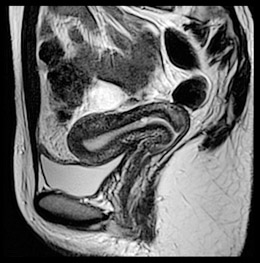

Vantage Titan 3Tによる子宮画像

3Tでは課題となっていた躯幹部の信号強度むらが, “Multi-phase Transmisssion”により改善されます。3TのSNRを活かした,均一な画像が期待できます。

動き補正法“JET”により,腸管の動きを抑制できます。さらに,折り返し防止も併用できるので,アーチファクトの少ない鮮明な画像が得られます。